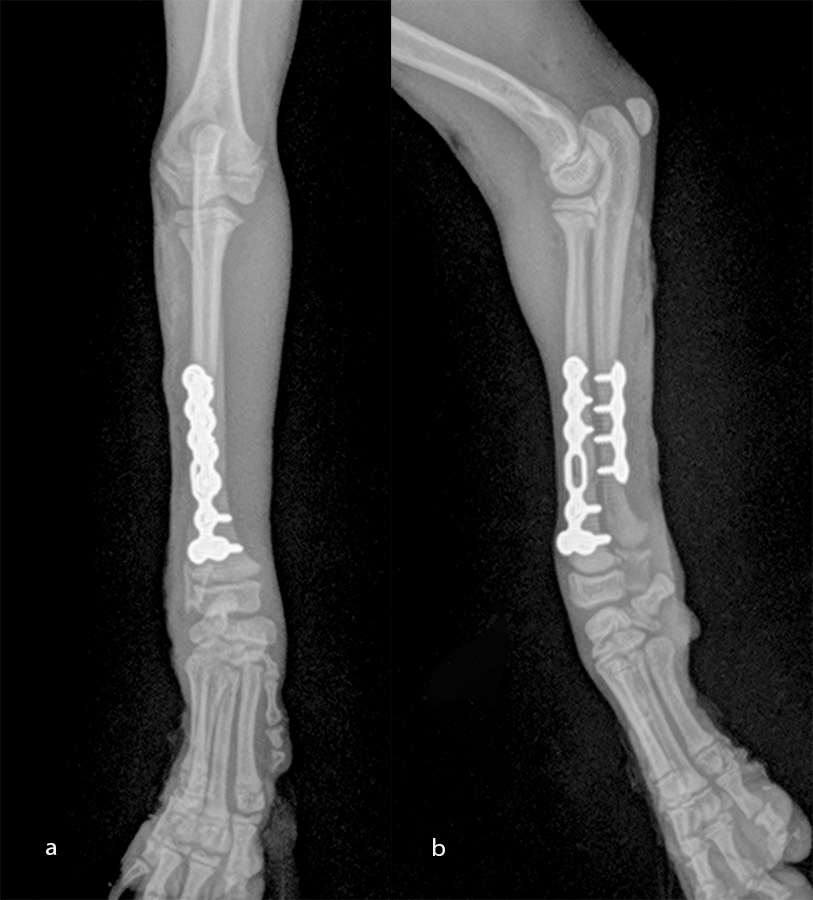

Open reduction and internal fixation of distal radial and ulna fractures with a 1.3 radial plate and a 1.3 ulnar plate (Fig 10).

The patient was a 2.5-month-old, 1 kg Japanese Spitz dog presenting with a radial-ulna fracture of the left thoracic limb after a jump from the sofa. The LCP 1.3 T-plate was perfectly adapted for the distal radial fracture. As the dog was "active" and as the ulna was about the same size as the radius (Fig 11), a four-hole LCP 1.3 adaptation plate was used on the ulna.

An open but do-not-touch approach was performed, and the plate was fixed with both cortex screws and locking screws for both plates (Fig 12). After 4 months, the fractures were totally healed with normal bone growth and the dog had a complete functional recovery (Fig 13).